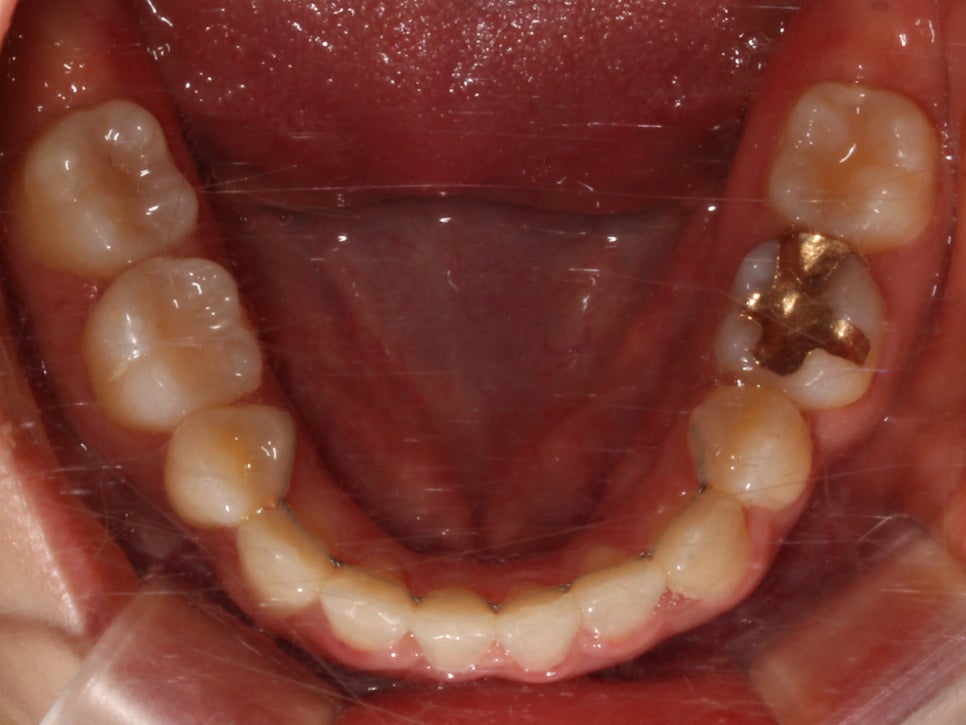

상악과 하악의 교합면이 고르지 못하고

덧니로 인해 치열에 총생이 생겨

심미적으로 좋지 못한 상태입니다.

하악의 경우 덧니로 인해 치아 사이의 공간이

매우 좁아 전치부의 치아가

삐뚤빼뚤해 보이기까지 합니다.